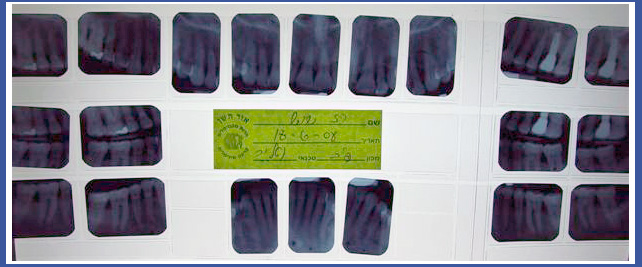

צילום סטטוס:

זהו צילום שנעשה במכון רנטגן וכולל 14-18 צילומים פריאפיקלים המכילים את כל השיניים בפה.

צילום סטטוס נעשה בדרך כלל כאמצעי אבחנתי לאנשים שעוברים\עברו טיפול שיקומי בפה, אנשים שיש להם בעיית נסיגת עצם והחניכיים –הצילום מאפשר לראות את גובה העצם המאחזת את השיניים.

במקרים רבים רופא השיניים יבקש מכם להביא צילום סטטוס הכולל גם צילומי נשך בערכה אחת.

צילום סטטוס מקביליות:

במקרים רבים רופא השיניים יפנה אותך לבצע צילום "סטטוס מקביליות" . ובכן זהו בעצם הדבר האמיתי ולא צילום הסטטוס הרגיל..

הצילום בנוי מ 20 צילומים פריאפיקלים (בודדים), כאשר לצילום זה יצורפו תמיד גם 4 צילומי נשך.

בצילום זה משתמשים בפילים צר יותר לשיניים קדמיות ובכל צילום מתמקדים בשן אחת בלבד, בניגוד לסטטוס רגיל שבפילים אחד מתמקדים בכמה שיניים במקביל.

בצילום סטטוס מקביליות, הצילום עצמו מוחזק בפה באמצעות מכשור פלסטי נקי ,אסתטי וברוב המקרים אף סטרילי. הקרן ממוקדת ואינה מתפשטת לצדדים.

הצילום קרוי בשפה מקצועית "אורתורדיאלי" והוא בעצם כמו "צל" של השן , אמנם מוגדל אך ביחס דומה.